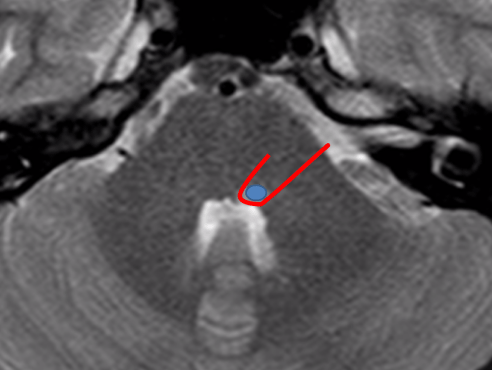

En estas imágenes se puede observar en la figura 1. una lesión localizada en el suelo del IV ventrículo, en la teórica localización del VI par craneal. El núcleo del VII par craneal se encuentra por delante e inferiormente, de ahí emergen las fibras motoras que realizan un recorrido ascendente y posterior «abrazando» al núcleo del VI par craneal. En la figura 2. en azul aparece el VI par craneal y en rojo está el «teórico» recorrido del VII facial.

En este caso el paciente acudió a urgencias para consultar por una pérdida de movilidad de la hemicara izquierda «periférica» y en la exploración presentaba una diplopía (visión doble) por afectación del VI par craneal. La naturaleza de la lesión fue inflamatoria y se diagnosticó posteriormente de Esclerosis Múltiple.